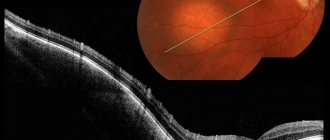

• Ультразвуковая диагностика (УЗИ) — исследование размеров, структуры, размеров и глубины новообразования.

• Компьютерная томография (КТ) — посрезное сканирование пораженной области.

• Магнитно-резонансная томография (МРТ) — подробная послойная визуализация гемангиомы и окружающих тканей.